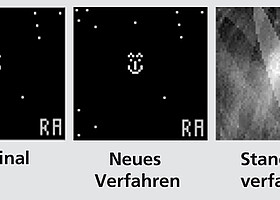

Determine ventricular far field with catheter

Computer system improves signals from ablation catheters in cardiac arrhythmias by calculating the ventricular far field in unipolar electrograms in the atrium.